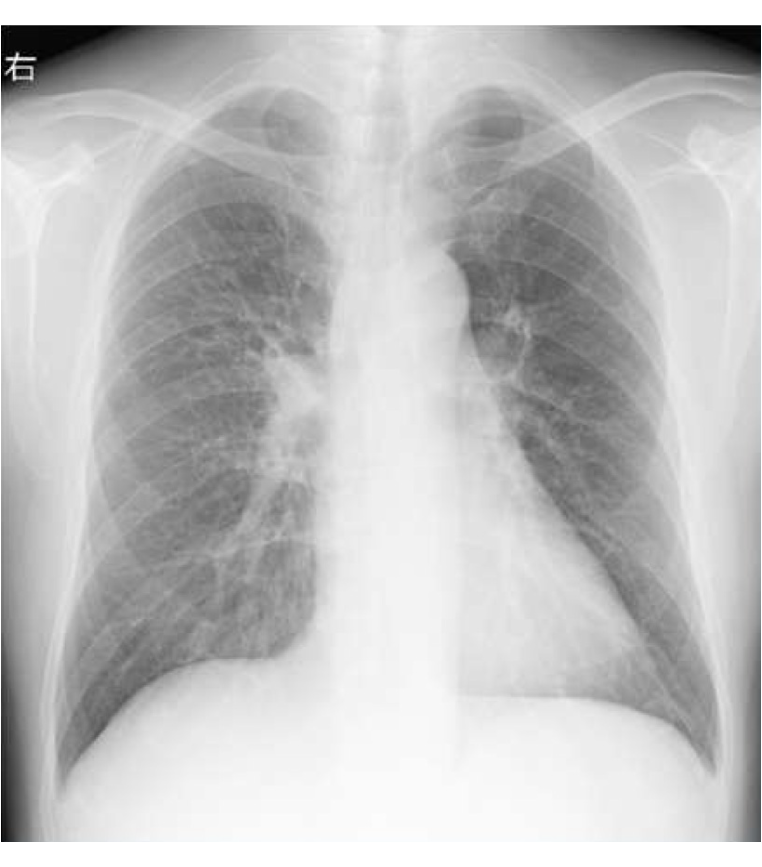

・胸部X線

心拡大の有無などを確認します。

心拡大や肺の異常の有無を確認します。

・胸部X線検査

肺の形・影の有無を確認する基本的な検査です。